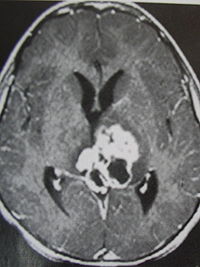

影像学表现

1.CT表现:

①肿瘤最常见于松果体区,位于鞍上区肿块常累及漏斗;

②CT平扫多呈等密度或稍高密度肿块,无出血、坏死及囊性变,可分叶,但境界清楚;瘤体本身钙化少见,典型松果体区生殖细胞瘤常见肿瘤包埋松果体钙化灶。

③增强扫描呈中等至明显的均匀强化。

④室管膜下转移可表现为沿脑室壁线状或条片状强化,沿脑脊液向蛛网膜下腔播散表现为脑表面、脑池的线状或结节状强化。

2.MR表现:

①最常见于松果体区,也常见于鞍上,可同时或单独存在。

②T1加权为略低信号或等信号,T2加权常呈等信号或高信号。

③增强后;呈明显均匀一致强化,并能发现沿脑脊液或室管膜转移的病灶。